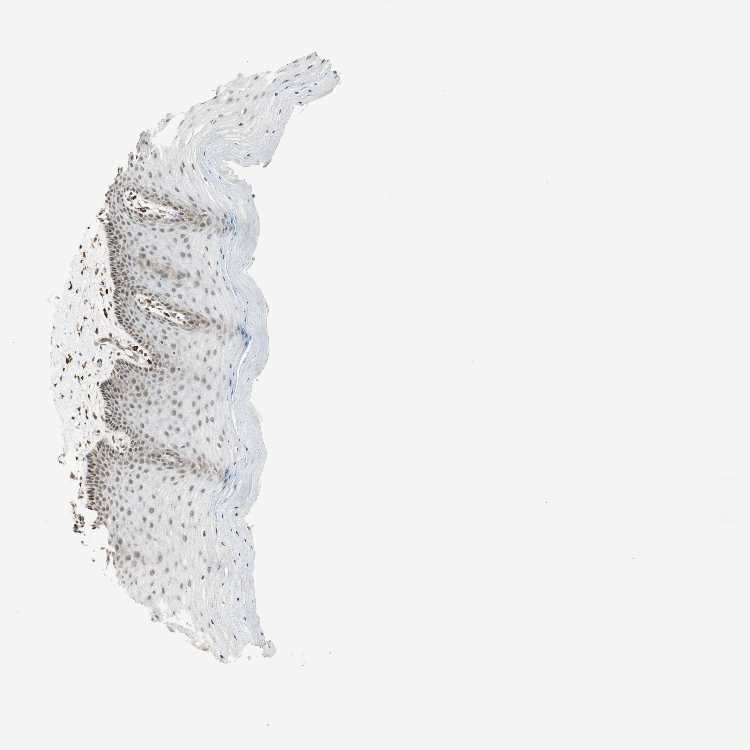

CERVIX - Antibody stainingi

Antibody staining in the annotated cell types in the current human tissue is reported as not detected, low, medium, or high, based on conventional immunohistochemistry profiling in selected tissues. This score is based on the combination of the staining intensity and fraction of stained cells.

Each image is clickable and will lead to virtual microscopy that enables deeper exploration of all samples and also displays staining intensity scores, fraction scores and subcellular localization as well as patient and tissue information for each sample.

Antibody HPA003150Antibody HPA018683

Glandular cells HighMedium

Squamous epithelial cells HighMedium